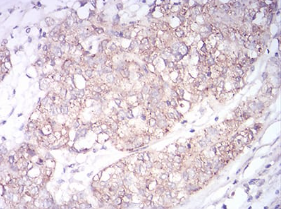

SK2 Mouse Monoclonal antibody[9C5E1]

This gene encodes one of two sphingosine kinase isozymes that catalyze the phosphorylation of sphingosine into sphingosine 1-phosphate. Sphingosine 1-phosphate mediates many cellular processes including migration, proliferation and apoptosis, and also plays a role in several types of cancer by promoting angiogenesis and tumorigenesis. The encoded protein may play a role in breast cancer proliferation and chemoresistance. Alternatively spliced transcript variants encoding multiple isoforms have been observed for this gene.

Species Reactivity:    Human

Immunogen:    Synthesized peptide of human SK2 (AA: 36-52).

IHC    1/200 - 1/1000